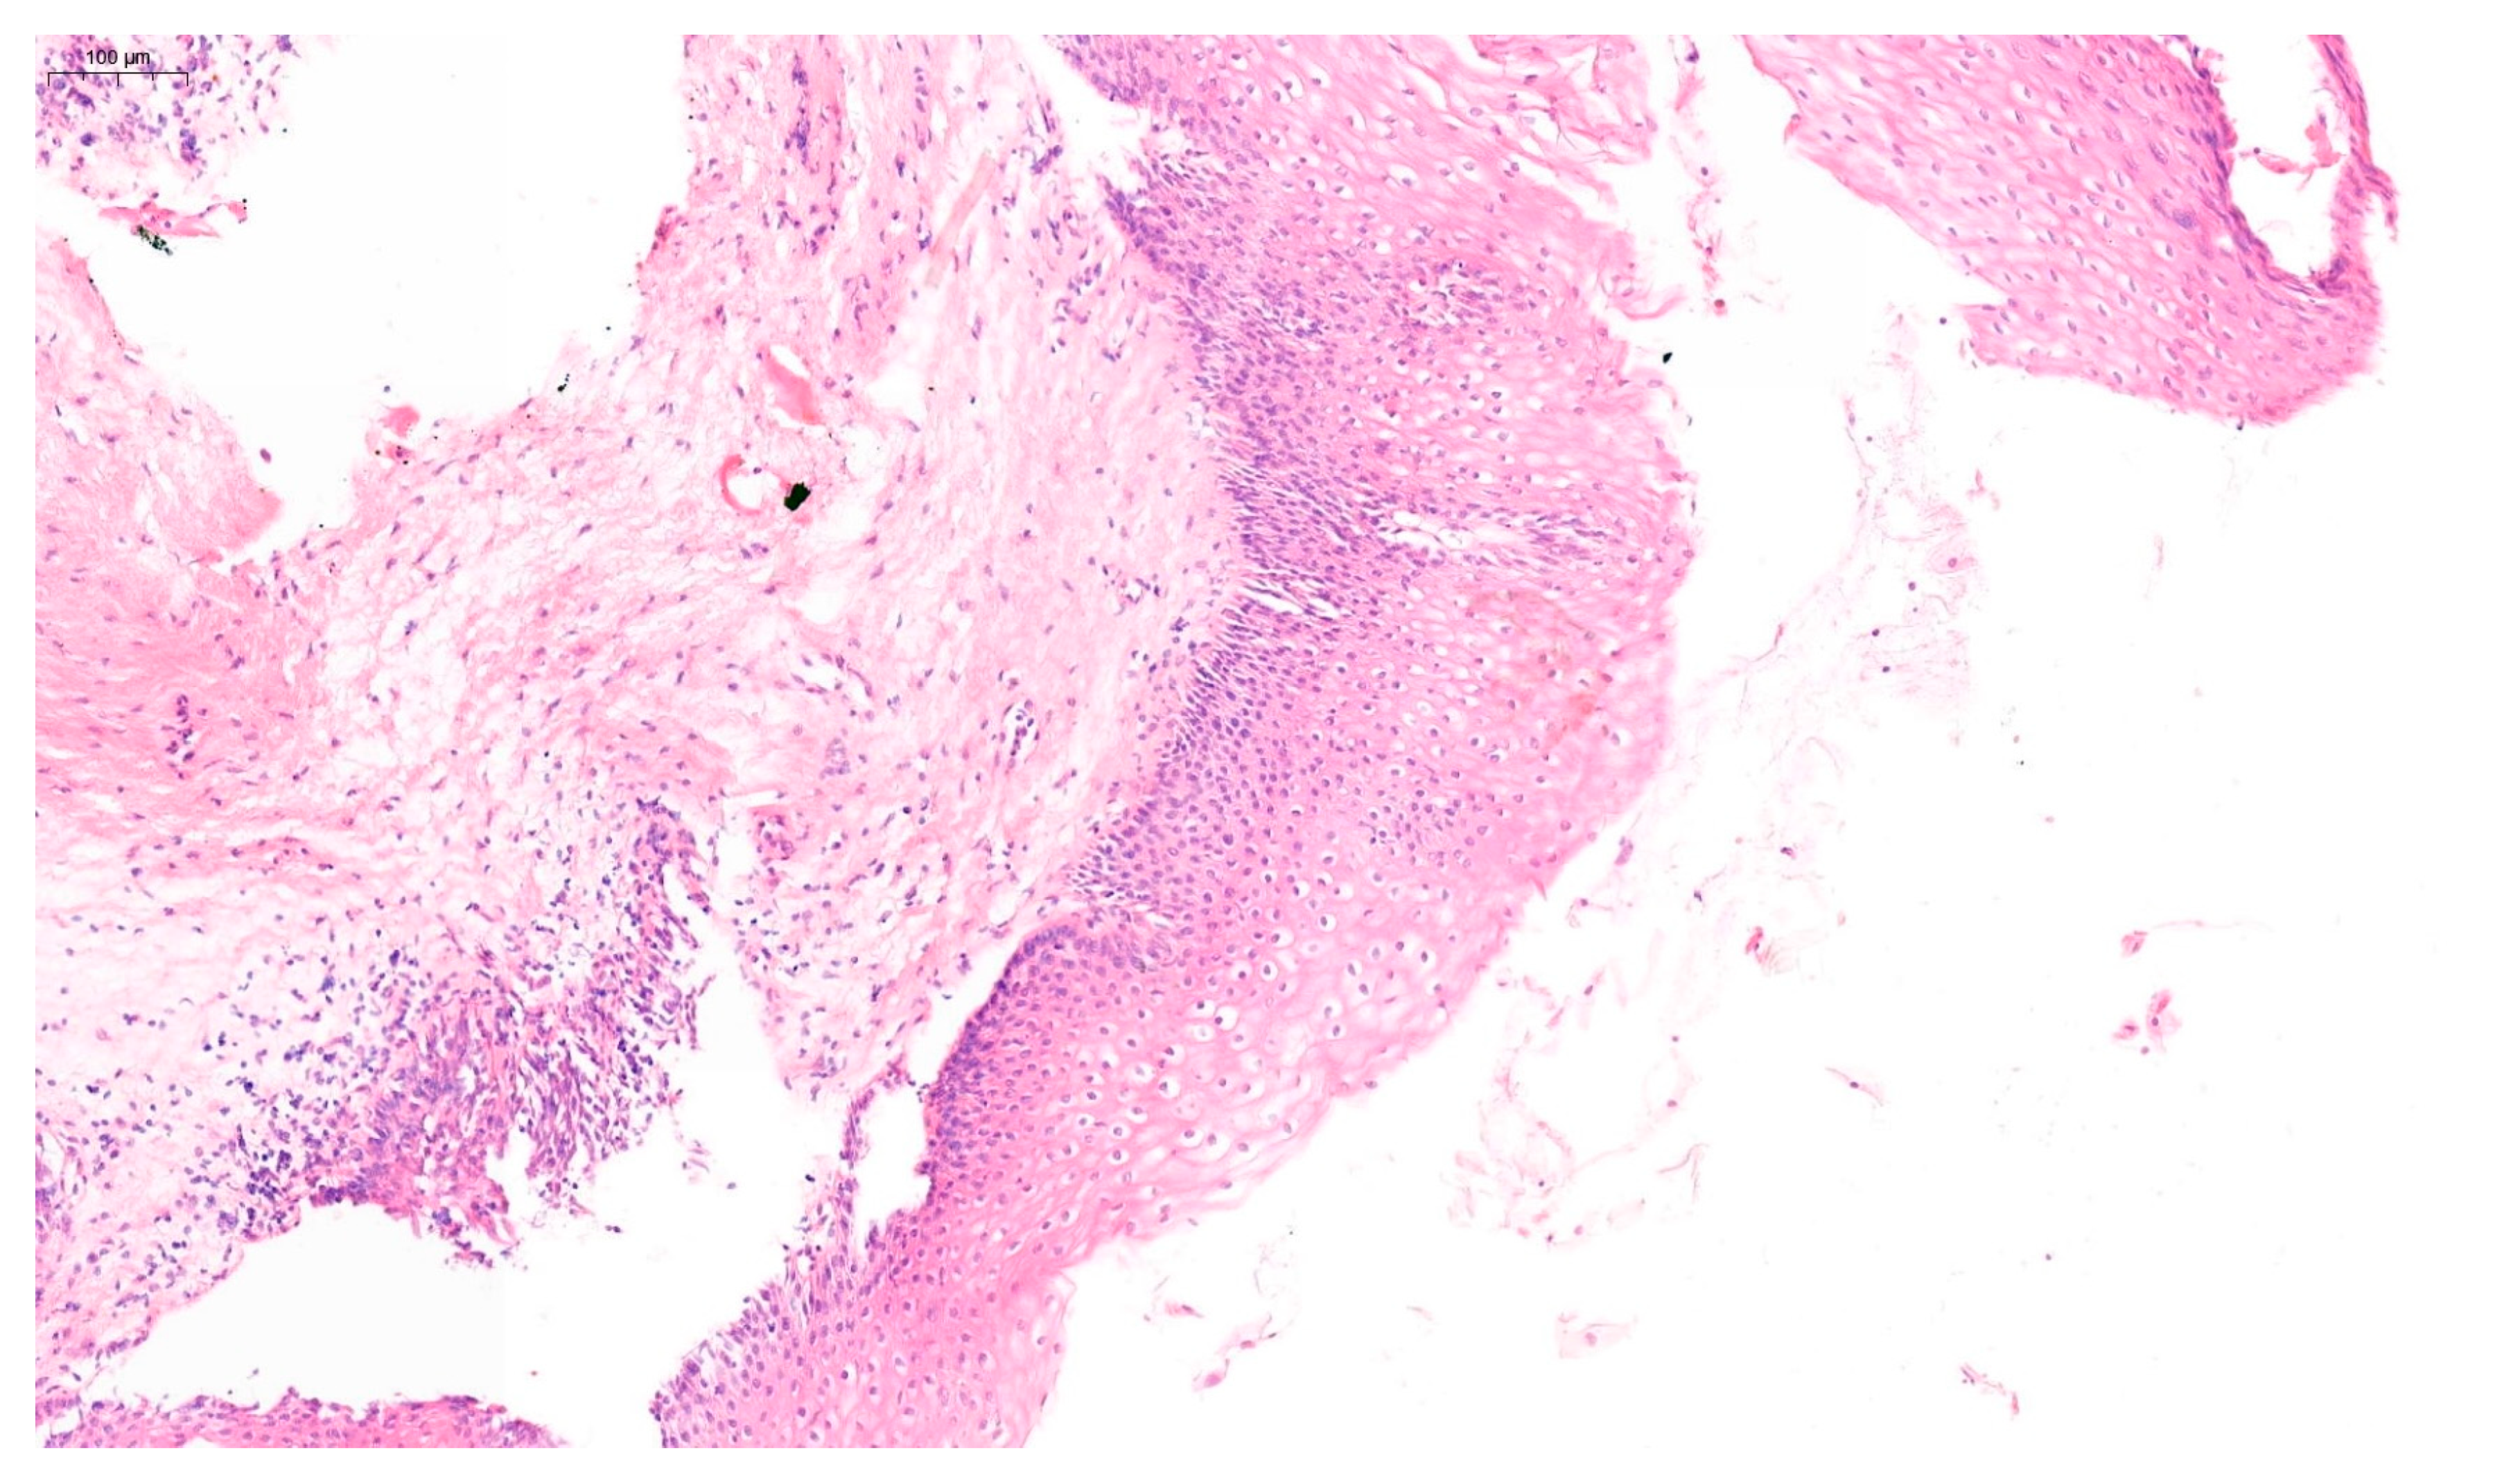

Furthermore, in approximately 75% of women, VaIN coexists with cervical or vulvar cancer [17]. The 2020 World Health Organization (WHO) classification distinguishes between low-grade squamous intraepithelial lesions (LSIL), which include VaIN 1, and high-grade squamous intraepithelial lesions (HSIL), including VaIN 2 and VaIN 3 [18]. Examples of VaIN 1 and VaIN 2+ lesions in patients from our cohort are shown in Figure 1 and Figure 2, respectively. Numerous studies have reported the risk of HSIL progressing to vaginal cancer ranging from 2% to 12% [19,20]. VaIN is treated in several ways, including CO2 laser ablation, photodynamic therapy, topical imiquimod, excisional surgery, electrocoagulation diathermy, or brachytherapy [9,21,22]. Therefore, VaIN is still a major diagnostic and therapeutic challenge, and further research is needed.

Figure 2. Histopathological image of VaIN 2/3, demonstrating marked nuclear pleomorphism and loss of maturation involving more than two-thirds of the epithelial thickness. Hematoxylin and eosin stain (H&E), original magnification ×200.